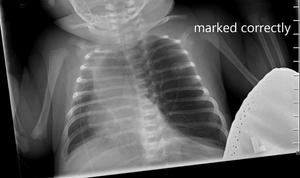

On physical examination, the patient appeared to be in significant respiratory distress. Her oxygen saturation was 96% on high-flow nasal cannula.

Can you diagnose this patient? Take our poll and find out! Then check back for the full case, differential diagnosis, and correct diagnosis.